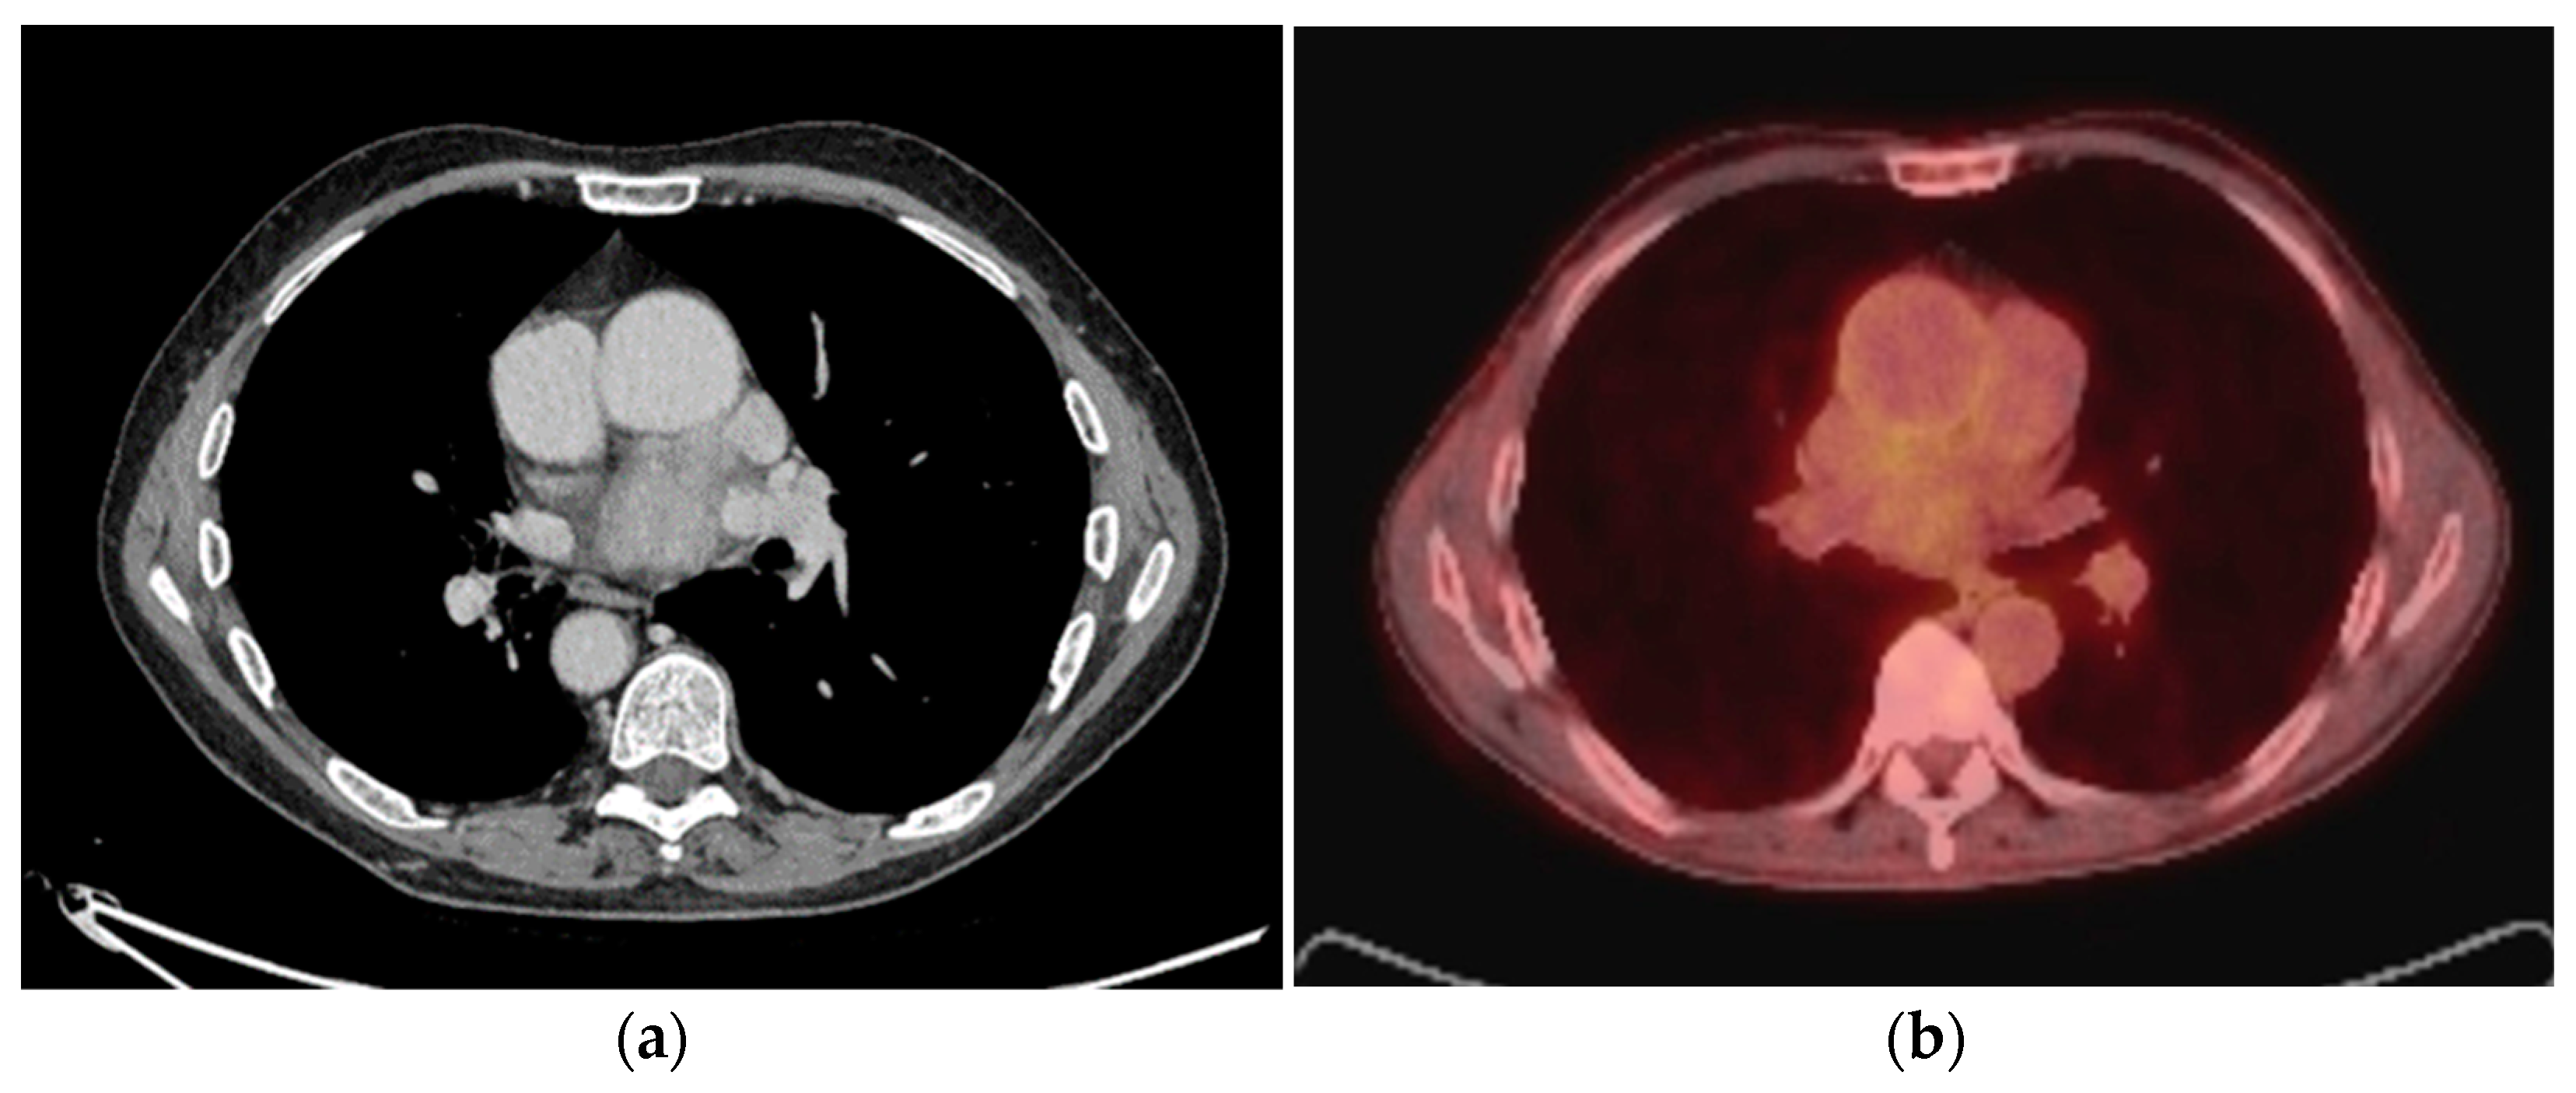

3. Mediastinum